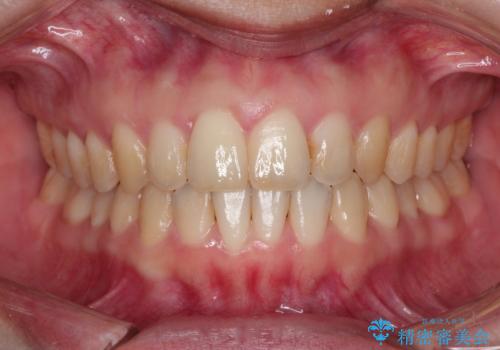

再矯正症例 前歯のガタガタと噛み合わせのズレをマウスピースで治した症例

コンプレックスだった前歯のガタガタがここまで綺麗になるなんて!!